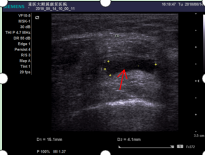

图一(箭头所指黑色区域为关节积液)